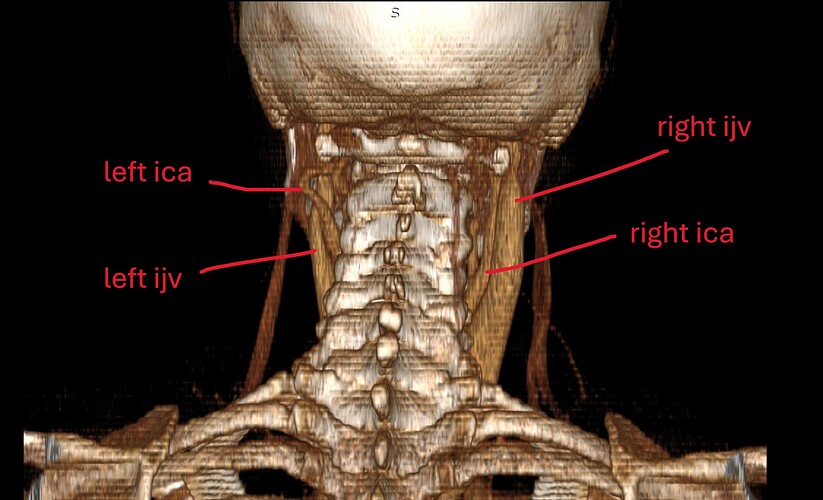

I did have an MRA done at Mayo that showed severe blood flow compression on my left side with my arms up. Because of this test, I went back to UCLA and did tests for Thoracic Outlet Syndrome. The limited tests they can do for this seemed to help. So, I had a left rib resection 2 yrs ago. Before this surgery, I did do a CT w/wo contract to look for Eagles and the report came back saying my stylohyoid was normal. So I went ahead with the thoracic outlet surgery. That surgery got rid of the daily headache I was dealing with. It seemed to have relieved pressure headaches and some of the loss of feeling in my arm. It never helped with the facial pains and dizziness though that I live with. Months after this surgery, I also developed Frozen Shoulder. I found it odd I got this so long after the surgery and when I was in PT. It seemed like the more we tried to use my arm and mess with my neck, the worse it got. I then went back to Mayo and had a head and face MRI that showed compression of my vagus nerve with an artery around my brainstem. It also showed a blood vessel touching my trigeminal nerve which is what they look for with trigeminal neuralgia surgery. So I took this and followed this lead. After visiting three trigeminal neuralgia surgeons, most of them said since I didn’t live with shooting lightning pains, I wasn’t a good candidate for the surgery. I was referred to some neurosurgeons regarding the vagus nerve compression at the brain stem. I almost had surgery booked for this and then the dr said something more is going on here, let’s hold off. This led me to circle back to Eagles Syndrome. Even though my CT hadn’t shown eagles on the report, I took it to Dr. Osborne. He indicated I had a calcified ligament. I almost moved forward with surgery, but I am concerned about the vascular issues I know I’m experiencing. I worry that I need to ensure we target these issues in my surgery. In the past few years, I’ve had near fainting spells, dizziness (I no longer can drive), BP issues that were similar to POTS but not, heart palpitations, horrible brain fog, and a complete inability to concentrate. I also get left sided body numbness and weakness. My left leg can even be impacted. It’s not to where I can’t walk but it feels like I’m living on a cruise ship trying to balance myself and my left side is weak. I feel like I need to confirm I have vascular issues and make sure I care for this in surgery. I tried to get a second opinion with an ENT at UCLA and they said they saw nothing wrong with my stylohyoid but that they see something wrong with my hyoid bone that they might be willing to operate on.

I really need help reading my images myself. I have anonymized them, but I don’t even know how to provide the right image to view here. I want to be able to advocate well for myself but I need to know what I’m looking at. I feel like the group on here know more than any doctors at this point. I would love to get back to normalcy…driving my kids around, actually getting sleep, being able to think clearly, being able to physically exercise, to be thriving and not barely surviving. Things I took for granted before this, I won’t again. Pls help if you are able. I can post my images following this first post though guidance on steps would be appreciated.